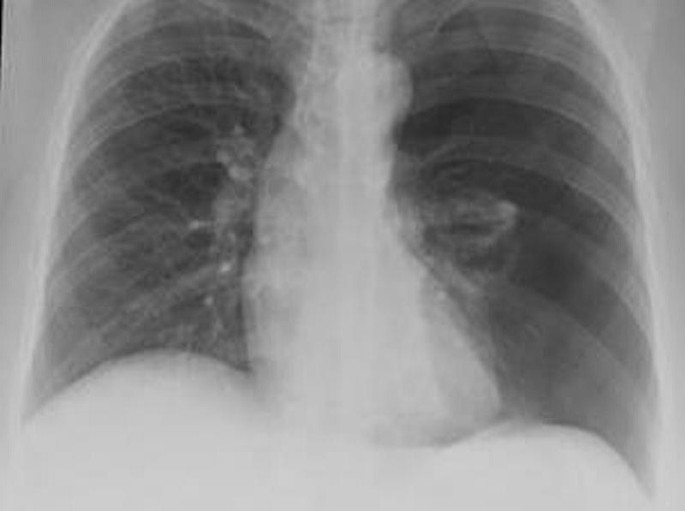

Chest x-ray showing bilateral pneumothorax with a flattened diaphragm... | Download Scientific ...

Chest x-ray showing bilateral pneumothorax with a flattened diaphragm... | Download Scientific ... from www.researchgate.net

Catamenial pneumothorax: A case report

Catamenial pneumothorax: A case report from www.jpma.org.pk